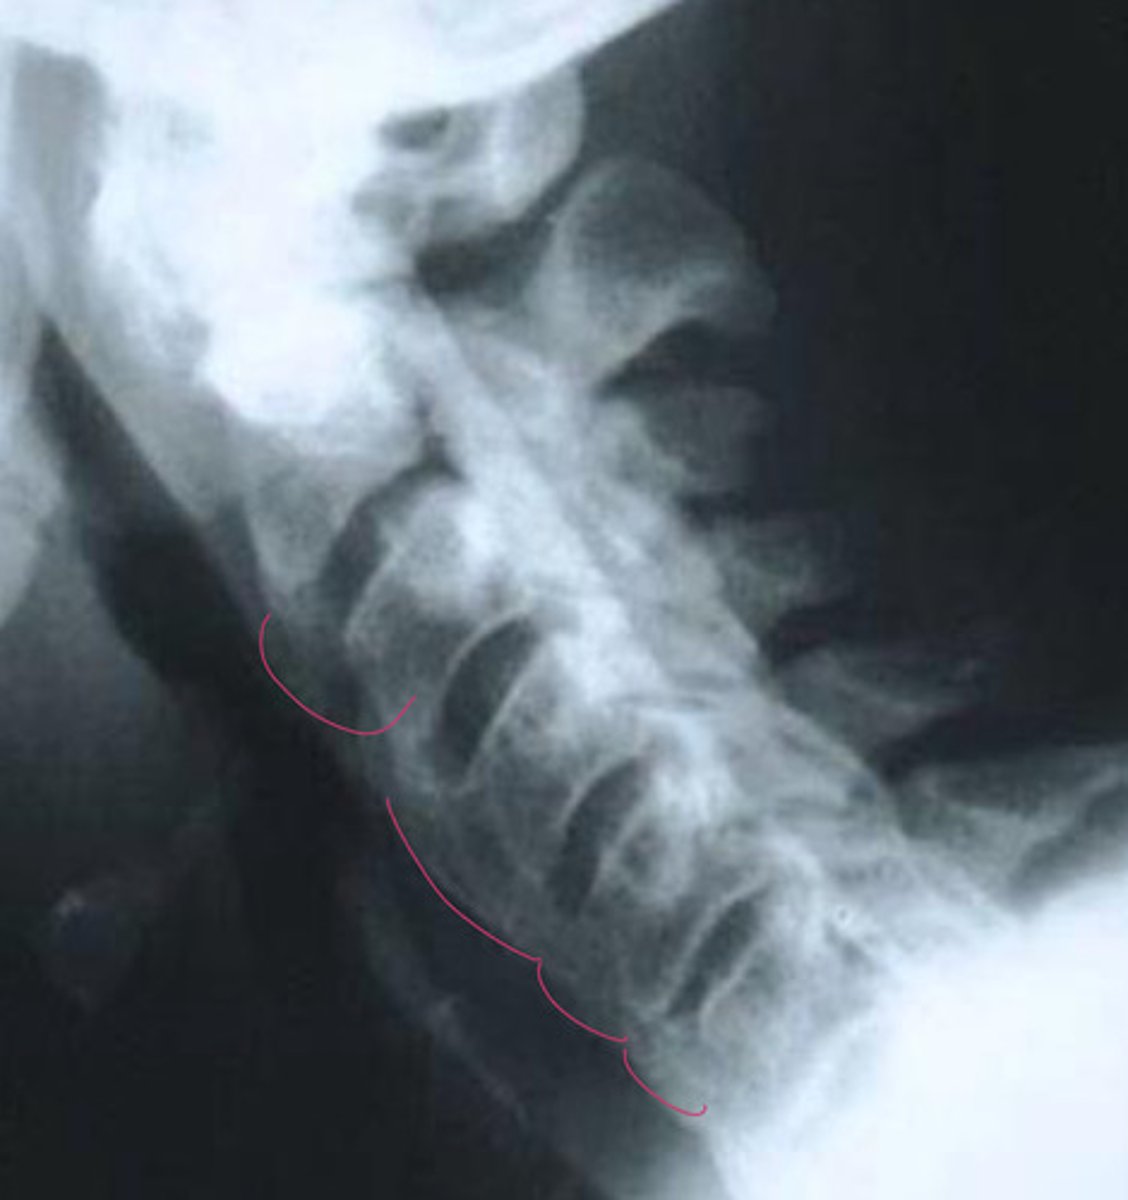

16, 14, 13, 12, 12, 12

What is the lateral sagittal canal size for each cervical

Back of dens to spinolamina line

How do you measure the lateral sagittal canal size of c1?